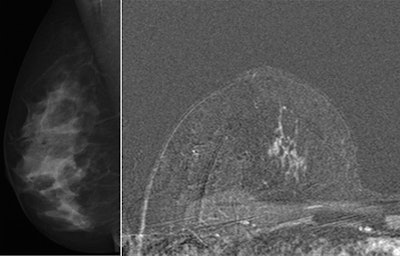

![]() Breast MRI can detect pathology not found on conventional mammography. Breast MRI scan (right) shows ductal carcinoma in situ not found on mammography image (left). Images courtesy of Dr. Christiane Kuhl, University of Bonn, Germany. |